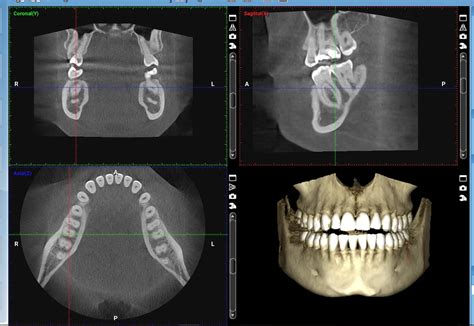

El CBCT (Cone Beam Computed Tomography) es una herramienta valiosa para la colocación segura de implantes. Permite realizar mediciones precisas entre el reborde alveolar y el piso del seno maxilar, facilitando la planificación de cirugías de elevación del seno para aumentar la altura del hueso alveolar.

Imagen de un CBCT utilizado en la planificación de implantes dentales.